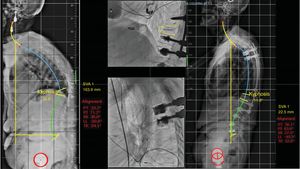

In patients who present with a rigid angular kyphosis (1 B), if compensated, treatment could be conservative. This scenario is rare and usually occurs in the thoracic area.7 If it is located in the thoracolumbar hinge or at the lumbar level, surgery may be necessary (Fig. 6). Multiple surgical options have been described. There is the traditional open posterior approach with a pedicle subtraction osteotomy initially described by Heinig in 1985 with the ‘eggshell’ or decancellation technique,18 with the inherent risk of bleeding and neurological complications with the classic technique. The combined anterior and posterior approach has also been described to perform an anterior arthrodesis by corpectomy and placement of an intersomatic cage combined with a posterior approach.12 The advantages of this approach are direct decompression of the vertebral body fragments compressing the canal and solid reconstruction of the anterior spine. Good results have been published with this technique, but due to the osteoporotic nature of the fracture, and the frailty of the patient, combined approach surgery may prolong surgical time and increase the risk of bleeding and complications related to an anterior approach (lumbar, thoracolumbar, or thoracic). Implant subsidence in osteoporotic bone has also been reported. Suk et al. compared both approaches,19 and concluded that the posterior approach offers advantages over the combined approach, such as better correction of kyphosis and less surgical time and bleeding. Finally, recent studies have published promising results with a simplified decancellation osteotomy technique combined with minimally invasive instrumentation.20–22 This technique minimises bleeding and neurological complications, and improves postoperative pain control and functional recovery. In these cases where the patient is compensated, short posterior instrumentation (with two levels below the osteotomy and two to three levels above the osteotomy) can be performed with good results.

Illustration of a case with a stage 1 B C, showing that it compensates with a lumbar hyperlordosis mechanism (note a lumbar lordosis of 74° for a pelvic incidence of 54°). The patient was treated with a decancellation osteotomy and short instrumentation and normalisation of the lumbar hyperlordosis is observed on the 5-year postoperative control X-ray.